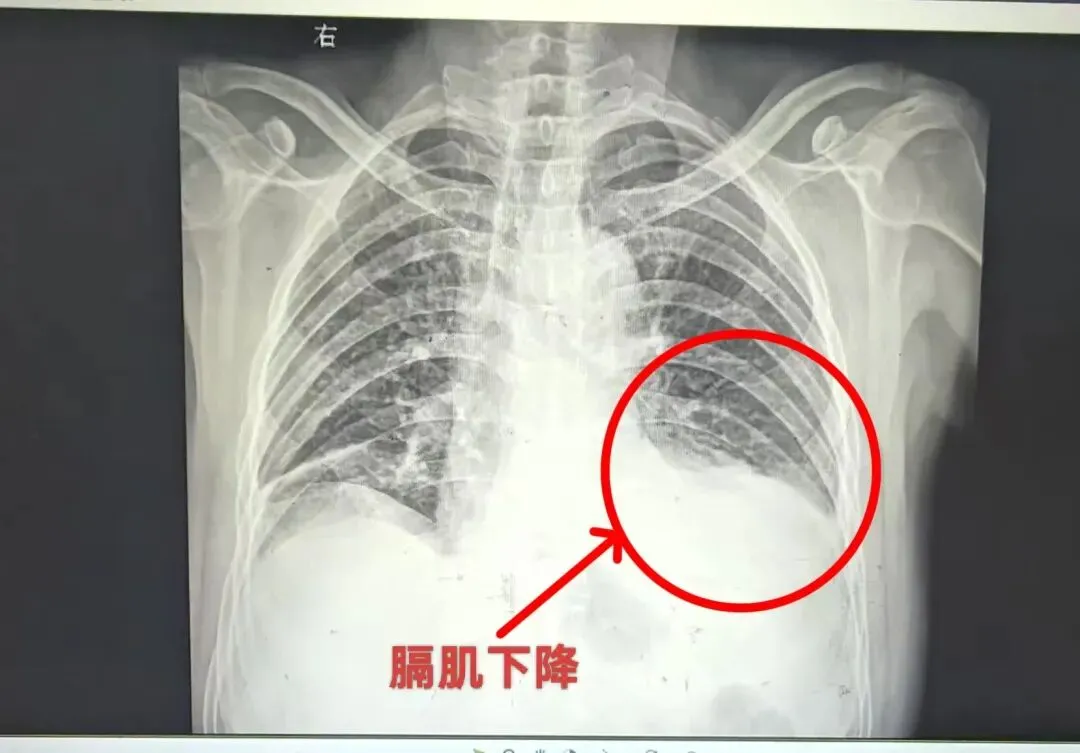

整个手术过程顺利,手术时长精准把控。术后患者安返病房,上腹部胀痛、胸闷气短等不适症状即刻缓解,复查影像学检查显示,左侧膈肌已下降至正常位置,手术效果立竿见影

术后复查胸部正位DR照片